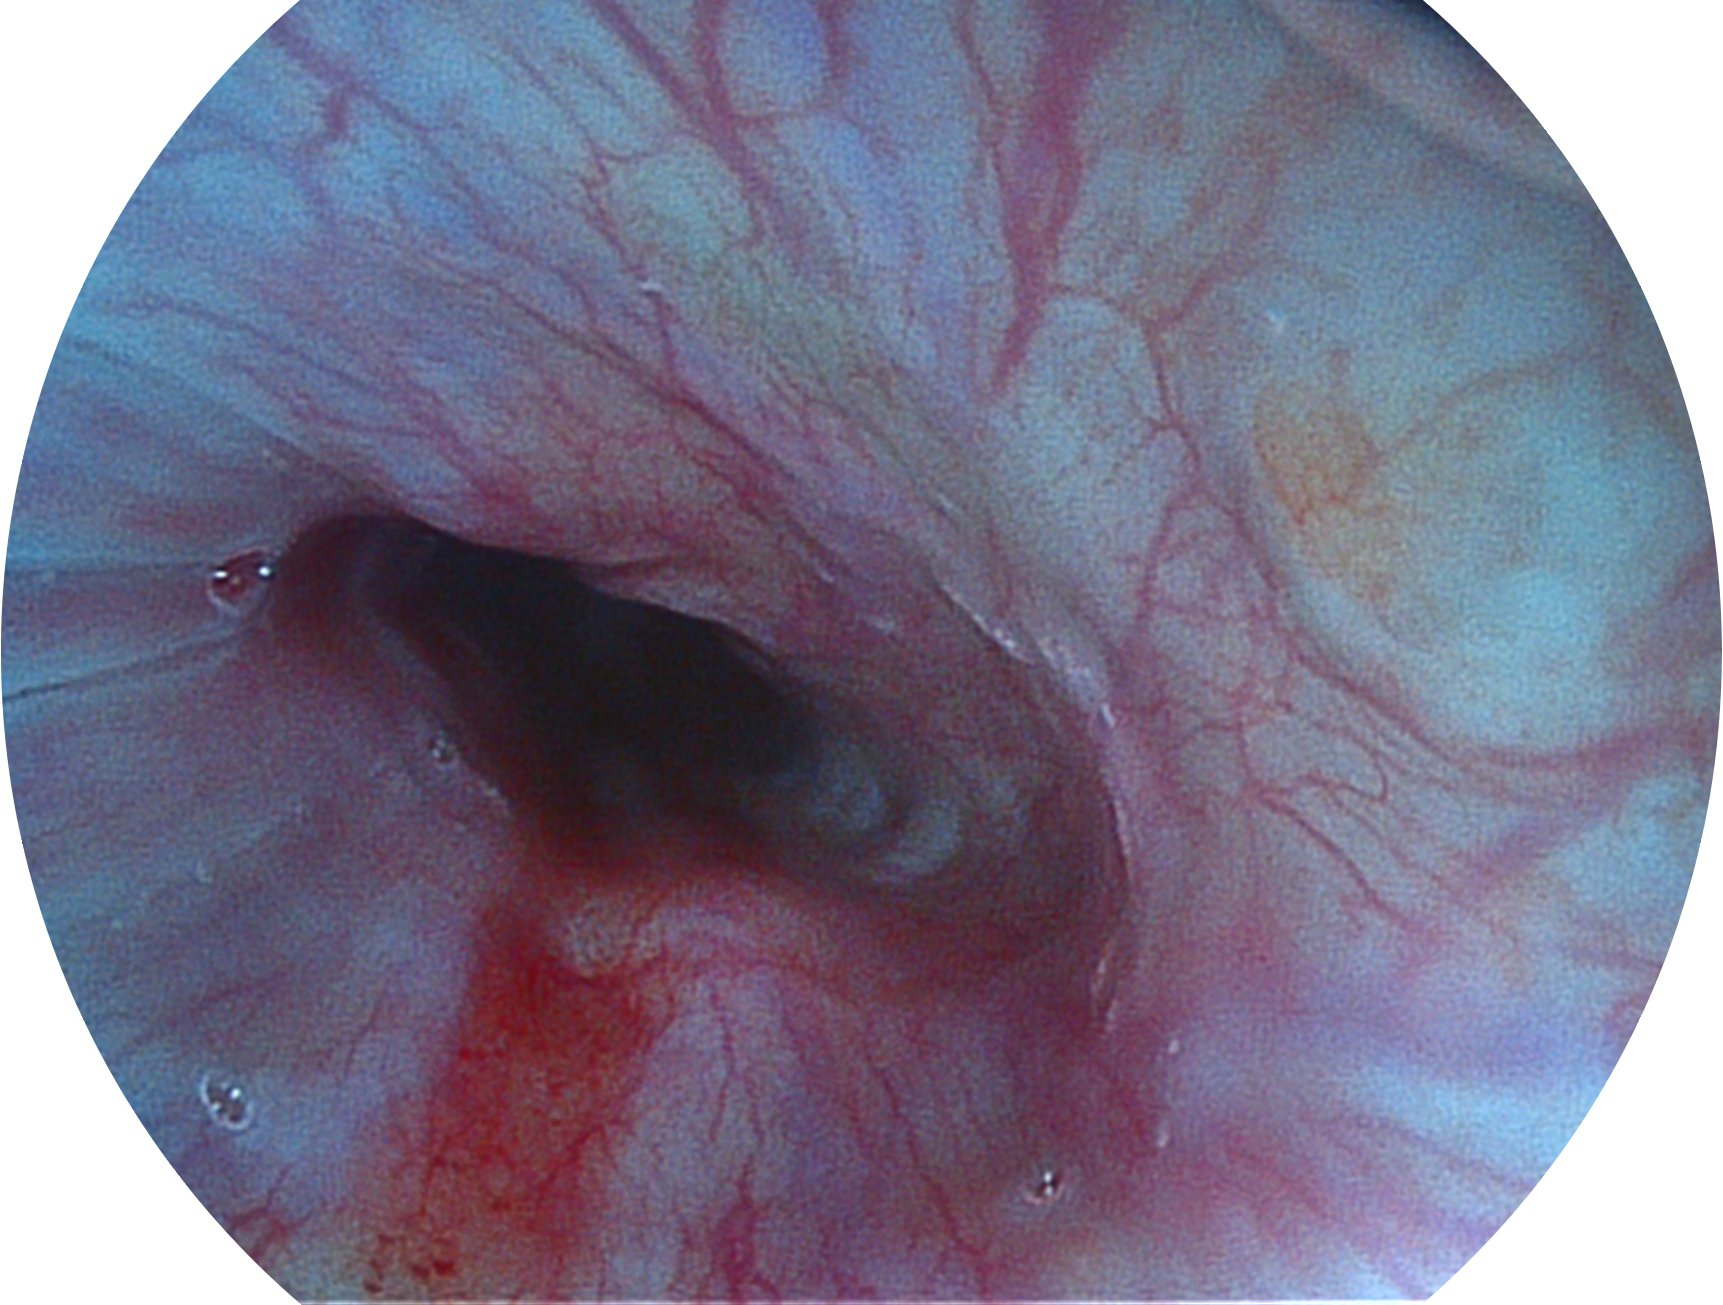

• 白光图像 VIST图像